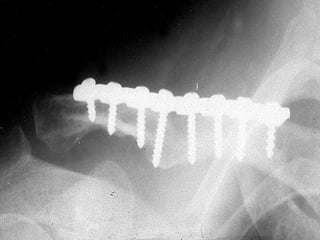

TRATAMIENTO

QUIRURGICO

VENTAJAS Y DESVENTAJAS

   Clavo centro-medular (poner presión

centro-medular)

   Trazo transverso

   Placa de tungsteno

   Trazo oblicuo

   En fracturas diafisiarias inestables

   Muy poco uso

   Muy poco usados en fractura distal, más en luxación.

   Todo material de osteosíntesis debe ser retirado una

vez realizado su trabajo